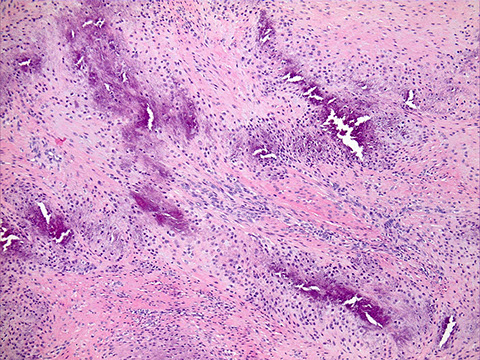

Epithelioid sarcoma

Epithelioid sarcoma. A, The tumor shows epithelioid morphology and moderate to severe cytologic atypia. The lesional cells are positive for cytokeratin (B) and erythroblast transformation-specific transcription factor (ERG) (C) and demonstrate loss of nuclear integrase interactor 1 (INI1) (D) (hematoxylin-eosin, original magnification x200 [A]; original magnifications x200 [B through D]